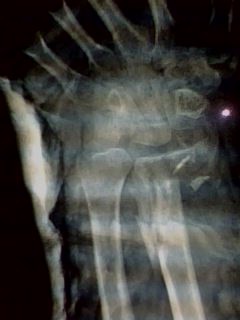

Se observa extremidad torácica

derecha con deformidad importante a

expensas de heridas por machacamiento en antebrazo hasta tercio proximal con

medio, con exposición muscular, tendinosa y ósea, sangrado moderado con

presencia de micelas, con crepitación a nivel de tercio medio y distal de

antebrazo y mano, incapacidad para los arcos de movilidad, pulsos radial y

cubital no palpables, llenado capilar de 1er dedo de 3”, del 2do al 5to. de

4-5”.

Fractura expuesta de radio y cúbito derechos IIIC de Gustilo y

Anderson

Fractura expuesta de radio y cúbito derechos 22C1.2 de AO, IIIB de Gustilo

Fractura-luxación periescafosemilunar

Sección de los músculos extensores del 3, 4 y 5to. dedos.

Se muestra la evolucion de partes blandas al mes de la intervencion.